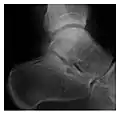

Figure 6: Subtle anterior talar fracture in a 39-year-old man presenting with ankle pain after a fall. (a) Anteroposterior radiograph shows a subtle oblique radiolucent line through the talus (white arrows). (b) Sagittal CT reformation confirms the presence of an anterior talar fracture with cortical offset (black arrow). Avulsion fractures, which consist of a detached bone fragment resulting from a ligament or tendon pulling away from the bone, may also present with subtle radiographic signs. Tiny osseous fragments near the presumed attachment site of a ligament suggest this diagnosis. Common sites are the lateral tibial plateau (the Segond fracture), the spinal tuberosity of the tibia resulting from anterior cruciate ligament avulsion, and the ischial tuberosity.[1]